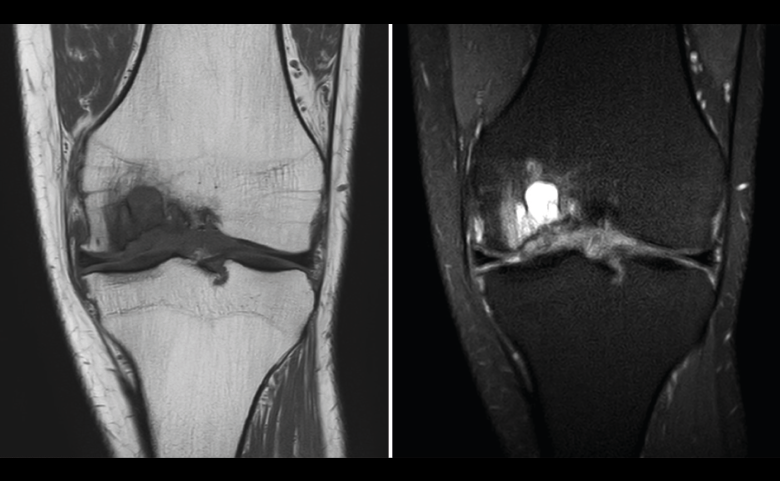

Figura 54. Corte de secuencia T1 y T2 Fat-Sat coronal de resonancia magnética: gran osteocondritis en el cóndilo femoral interno con edema en la medular adyacente.